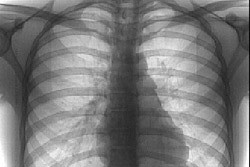

Рентгенологические исследования легких - это исследования, во время которых легкие пациента обследуются с помощью рентгеновского аппарата, при необходимости делаются снимки. Использование рентгеновского излучения позволяет точно оценить состояние легких и диагностировать заболевание. В дальнейшем, в зависимости от результатов рентгенологических исследований, могут быть проведены дополнительные исследования.

Обычно делаются две рентгенограммы легких. При выполнении так называемой передней рентгенограммы грудной клетки пациент спиной прилегает к источнику рентгеновских лучей, а за его грудной клеткой помещают кассету с рентгеновской пленкой, которая подвергается воздействию рентгеновских лучей. Пациент разводит руки в стороны. Второй снимок - боковой. При его выполнении пациент поворачивается боком к источнику излучения. Руку, находящуюся рядом с рентгеновской пленкой, он поднимает вверх, а другую - помещает за спину. Если одни ткани перекрывают другие, и дать точную оценку невозможно, то тогда делают так называемый поперечный снимок. Пациент поворачивается к источнику лучей на 45 градусов. Если врач хочет точно оценить верхушки легких, то для выполнения снимка пациент должен наклониться к источнику рентгеновских лучей, выгнув при этом туловище. При выполнении снимка, пока легкие подвергаются воздействию лучей, пациент должен сделать глубокий вдох и задержать дыхание (на 1 секунду). Во время выдоха легкие исследуются рентгеновскими лучами только при подозрении на определенные легочные заболевания.

В связи с тем, что бронхи и легочные альвеолы обычно наполнены воздухом, то легкие на рентгенограмме хорошо видны. Иногда изменения можно увидеть невооруженным глазом. Для получения более точных результатов используются специальные рентгеноконтрастные вещества.

На рентгеновском снимке можно четко увидеть ателектаз легкого, его доли или сегмента. Причиной ателектаза может быть опухоль, инородное тело или неполное расправление сети сосудов легкого. Кроме того, исследования позволяют проанализировать потемнения, которые характерны и для других заболеваний легких, таких, как воспаление легких, туберкулез, грибковые заболевания, опухоли, эдема и др. Анализ снимка предоставляет опытному врачу очень много информации о возможной причине потемнения.